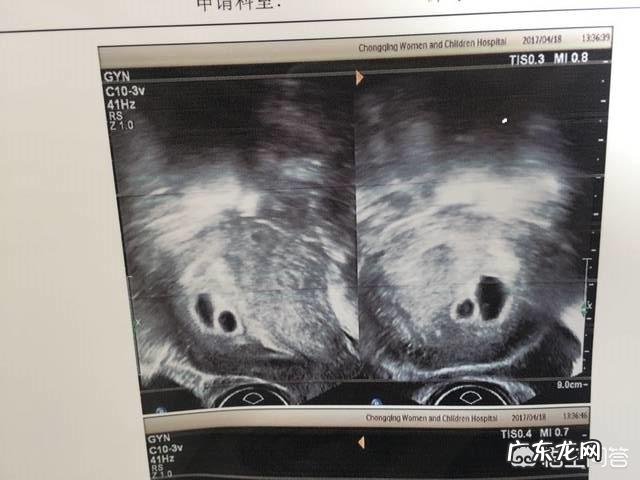

【怀双胞胎两个孕囊可以顺产吗】怀双胞胎两个孕囊可以顺产吗?我们幼儿园有个家长怀了双胞胎,现在已经六个多月 。她来接送老大上幼儿园的时候,和其他家长聊了起来去 。其中有一个家长听说是怀的双胞胎 。就赶紧说:“双胞胎是无法进行顺产的,所以你要做好准备哦 。”自己身边的几个例子说都是剖腹产的 。

那怀双胞胎的能不能进行顺产呢?其实这是人们的一个误区,怀双胞胎的并不是剖宫产的一个指征 。只要产妇身体条件以及胎儿满足顺产的条件是可以进行试产的 。